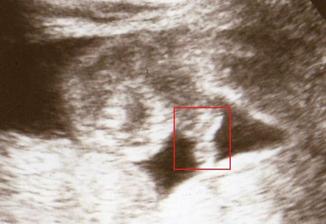

28.1.09-echokardiografie-srdíčko je v pořádku.Pan dr. nám ukázal pindíka,z holčičky se vyklubal kluk jako buk.